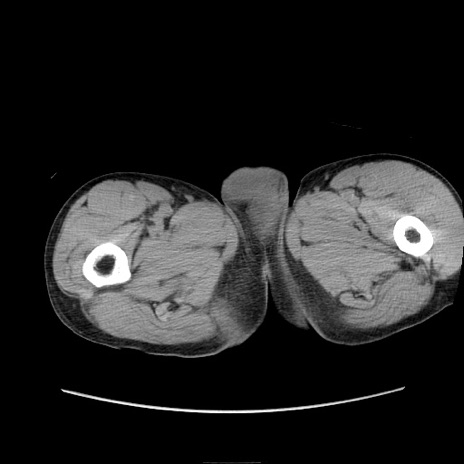

症例11(横断像)

症例

【症例】 60歳代男性

【主訴】 下腹部痛

【現病歴】 本日夜中より下腹部痛の症状認め、受診。

【既往歴】 膀胱癌(膀胱全摘+尿管皮膚瘻術) 、胃癌術後

【身体所見】 BT 35.3℃、PR 58/min、BP 136/98mHg、腹部平坦、軟、腸蠕動音±、ストマ留置あり、左上腹部~正中部に圧痛あり、反跳痛なし。

【データ】WBC 5100、CRP0.01